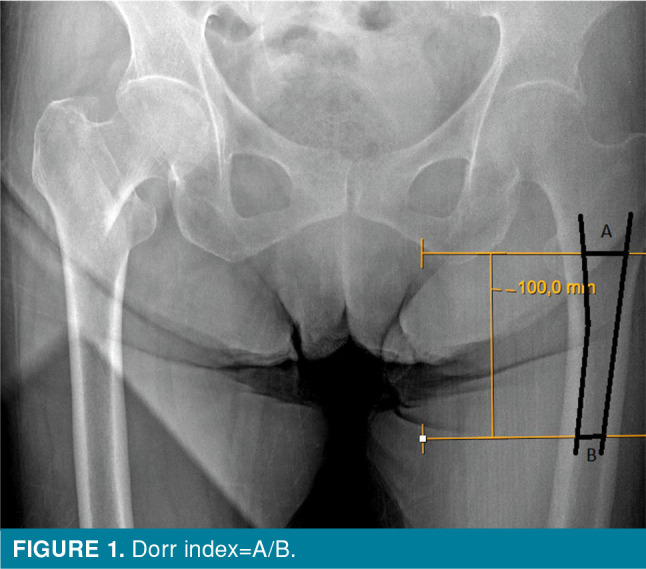

Patients and methods: This retrospective study examined 312 patients who underwent PFN for intertrochanteric fractures between January 2016 and January 2020. Patients with unstable fractures according to the AO/OTA (AO Foundation/Orthopaedic Trauma Association) classification, those over 65 years of age, with at least one year of regular follow-up, a tip-apex distance <25 mm, and a caput-collum-diaphyseal angle between 125° and 135°, were included. Seventy patients (19 males, 51 females; mean age: 72±3.8 years; range, 65 to 88 years) who met the inclusion criteria were included in the study. According to the Dorr index, patients were type A if the ratio was <0.5, type B if the ratio was between 0.50 and 0.75, and type C if the ratio was >0.75.

Conclusion: Dorr index is an important parameter that can be easily checked and used on preoperative radiographs to predict implant failure. The high probability of failure in the early period should be taken into account, particularly if PFN is planned in Dorr type C.